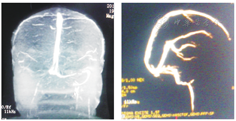

患者女,43岁。头痛3个月加重伴双眼胀痛、视力下降4天于2014年2月24日来我院眼科就诊。患者自述3个月前无明显诱因出现头颈部疼痛,呈跳痛,有时伴恶心,无呕吐,头痛发作前眼前无闪光、暗点等,亦无肢体麻木乏力感,无耳鸣、听力下降。于当地医院给予甘露醇治疗有效,但反复发作。入院眼部检查:双眼视力:0.8,双眼结膜无充血,角膜清亮,瞳孔直径约3 mm。对光反应稍迟钝,RAPD(+)晶状体透明,玻璃体清。双眼底:视乳头色淡红,边界不清,水肿隆起约2~3 D,视网膜静脉迂曲扩张,黄斑中心反光弥散,视网膜平伏(图1)。右眼压:12.5 mmHg,左眼压:11.0 mmHg。患者既往有冠心病史,于2010年在江西省人民医院行冠脉支架术。无糖尿病、高血压,无外伤等病史。血常规检查:血小板计数:580×109。脑脊液压力:250 mm H2O(正常120~180),显微镜及生化检查未见异常。眼底荧光素钠血管造影示:双眼视盘水肿(图2)。颅脑MRI、MRV、CT、眼眶CT均未见明显异常(图3)。全脑血管造影(CTA)示:考虑右侧横窦、乙状窦静脉血栓形成可能性大(图4)。明确诊断为:颅内静脉窦血栓形成,特发性血小板增多症,冠心病。

脑脊液检查对CVST诊断无特异性,但有助于查找CVST的病因并指导治疗。D-二聚体增高(>500 μg/L)有助于CVST的诊断。数字减影血管造影(DSA)是目前诊断CVST的金标准。治疗以降颅压、防脑疝、抗凝溶栓、抗痫、抗感染、改善微循环为主。抗凝治疗一般要维持3~6个月,治疗期间监测凝血系列。颅内静脉窦血栓形成单侧闭塞或双侧不完全闭塞,其预后较好;而大脑深静脉闭塞、上矢状窦合并横窦堵塞可导致颅内压持续升高,形成脑疝,预后多不佳。因此,对CVST应尽早明确诊断,合理治疗。